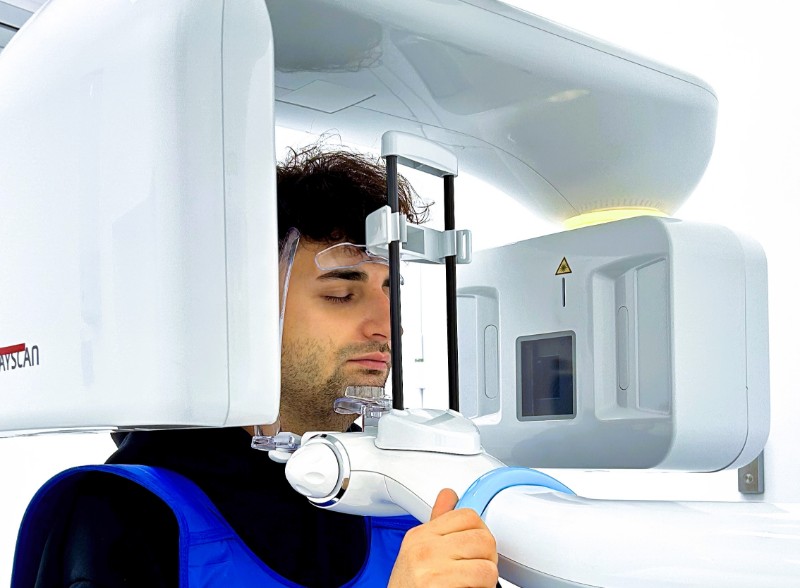

06.01.2026Успейте пройти точную диагностику гайморита, синусита и других заболеваний по специальной цене и получить полный цифровой архив снимков.

06.01.2026Успейте пройти точную диагностику гайморита, синусита и других заболеваний по специальной цене и получить полный цифровой архив снимков. -

12.08.2025Компьютерная томография (КТ) головы и шеи – один из самых информативных методов диагностики ЛОР-патологий.

12.08.2025Компьютерная томография (КТ) головы и шеи – один из самых информативных методов диагностики ЛОР-патологий. -